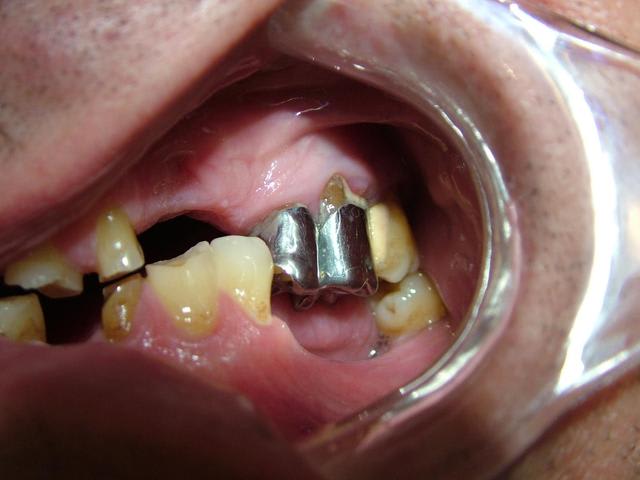

ce serait sympa de voir une photo en bouche qui sera plus parlante.

Super tes photos solene,

la mise en occluseur me parait erronée avec ce type d'abrasions les incisives devraient être en contact, mais pas grave l'essentiel c'est l'aperçu. ,

Cela me paraît risqué si tu parles de recouvrement incisif. Sur la photo ANT, l'abrasion est propulsive côté D et latérale côté G.

Merci pour toutes les réponses qui m'ont aidé à réfléchir au cas et surtout ne pas me précipiter sur mon plan de traitement stupidement. J'ai revu le patient il y a qq jours et je devais ce jour là lui faire la présentation du plan de traitement. Je lui ai expliqué que son cas était tellment complexe que je n'avais pas pour le moment de solution thérapeutique valable car je n'avais pas encore traité ce type de cas. Le patient a fort bien compris et j'en ai profité pour prendre des radios buccales ; en effet la mise sur occluseur que j'avais sur les précédentes photos était fausse. Le patient "occluse" différement. Voir les nouvelles photos jointes. Il y a très peu de contact antérieur ; j'ai bien demandé une dizaine de fois au patient de se mettre en occlusion pour arriver au même résultat que l'on voit sur les photos. Le patient a bien sur du mal à avoir un occlusion stable.

Ce qui m'interroge le plus c'est comment ce patient est arriver à user le bloc antérieur et arriver à cette situation. Il n'a pas d'habitudes nocives ( ex fumeur de pipes ou autres tics).

Il est vrai que la DV me semble conservé car il y a un calage postérieur côté droit et côté gauche.